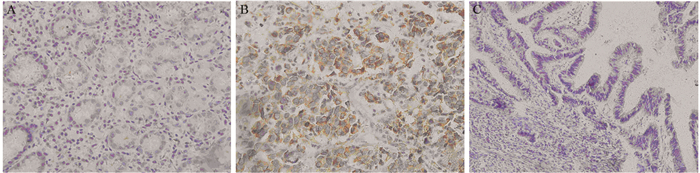

方法免疫组织化学法检测142例胃腺癌及25例癌旁正常胃黏膜组织中UCP2的表达情况,Pearson χ2检验分析其与临床病理特征的关系,Kaplan-Meier法及Cox风险回归模型分析UCP2的表达与胃腺癌患者预后生存的关系。将UCP2 siRNA转染SGC7901胃腺癌细胞系后,Western blot法检测UCP2蛋白的表达,EdU实验检测细胞增殖,划痕实验检测细胞迁移能力。

结果在胃腺癌组织中UCP2蛋白的阳性表达率明显高于癌旁正常胃黏膜组织(P=0.006),UCP2蛋白的表达与肿瘤浸润深度(P=0.024)、TNM分期(P=0.002)、淋巴结转移(P=0.001)显著相关;UCP2阳性患者5年生存率明显低于阴性患者(P=0.001)。在胃腺癌SGC7901细胞系中,UCP2高表达,沉默UCP2的表达能显著抑制肿瘤细胞的增殖,同时降低其迁移能力。

MethodsTotally 142 cases of gastric cancer and randomized 25 cases of normal gastric mucosa tissues in Tianjin Medical University Cancer Institute and Hospital were included. We used immunohistochemical staining to detect the expression of UCP2 and analyze its relationship with clinical pathological features. Kaplan-Meier method and Cox regression analysis were used to explore the correlation between the expression of UCP2 and the survival of gastric cancer patients. Western blot was used to detect UCP2 protein level after UCP2 siRNA transfection into SGC7901 gastric cancer cell lines. EdU assays and scratch assay were used to detect the proliferation and migration abilities.

ResultsThe expression of UCP2 in gastric adenocarcinoma tissues was significantly higher than that in adjacent normal tissues (65.5% vs. 28%, P=0.006). The expression of UCP2 in gastric adenocarcinoma tissues was significantly correlated with tumor infiltration (P=0.024), TNM stage (P=0.002) and lymph node metastasis (P=0.001). The 5-year overall survival of patients with positive UCP2 expression was significantly lower than those without UCP2 expression (P=0.001). Silencing UCP2 expression could significantly inhibit the proliferation and migration abilities of SGC7901 cell lines.